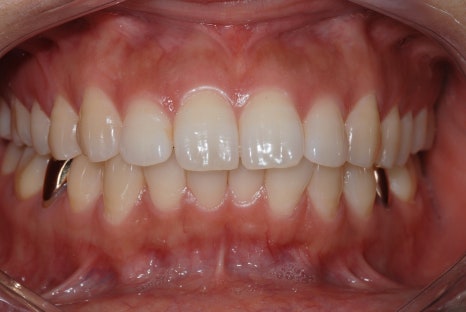

<교정치료 전후 사진>

치료기간: 23.05.15 - 24.10.21 (약 1년 6개월)

진행한 치료: 덧니, 치열 개선

치료기간: 23.01.18 - 24.6.04 (약 1년 6개월)

진행한 치료: 돌출, 중심선 개선

*치료 전후 사진은 환자의 동의하에 게재하였으며, 동일한 환경과 조건에서 촬영된 전후 사진입니다.